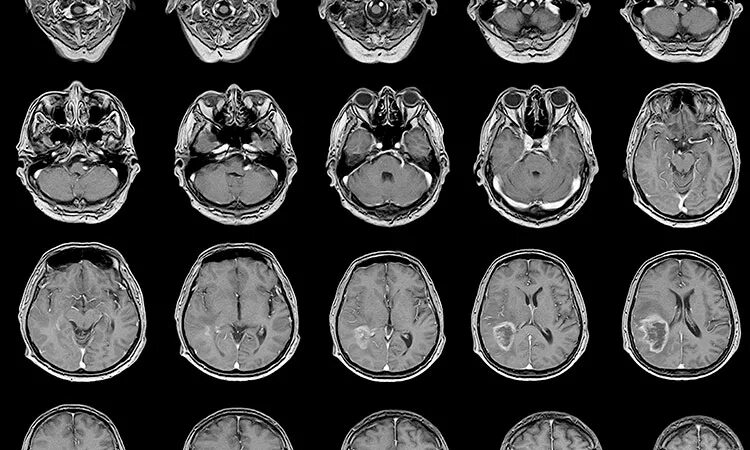

Что можно увидеть на мрт